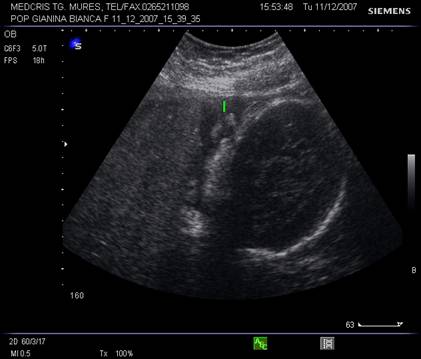

Dupa 13 saptamani in orbita apare si cristalinul in sectiunea parasagitala.

Fig. nr. 160 . Cristalinul hiperecogen, rotund in orbita dreapta .